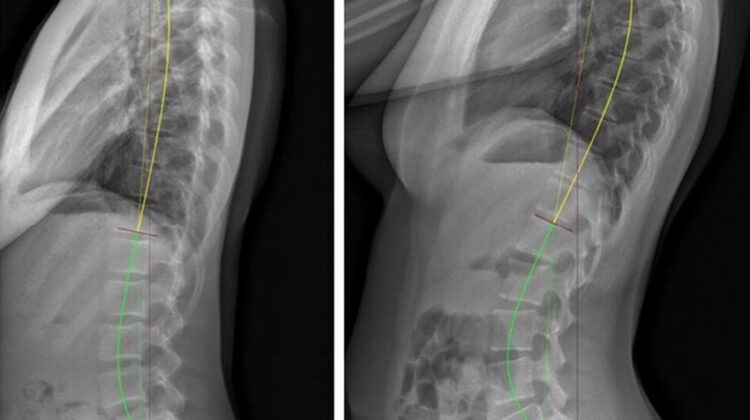

الأطباء حددوا نوعين رئيسيين من اختلال التوازن الجانبي:

الانحراف الجانبي للداخل (Concave CM): حيث يكون الجزء المائل من العمود الفقري موجهًا نحو الداخل بالنسبة للحوض.

الانحراف الجانبي للخارج (Convex CM): حيث يكون الجزء المائل من العمود الفقري موجهًا نحو الخارج بالنسبة للحوض.

كل نوع له طريقة علاج مختلفة، ويعتمد اختيار العلاج على شدة الانحراف وحالة المفاصل والعضلات المحيطة بالعمود الفقري.